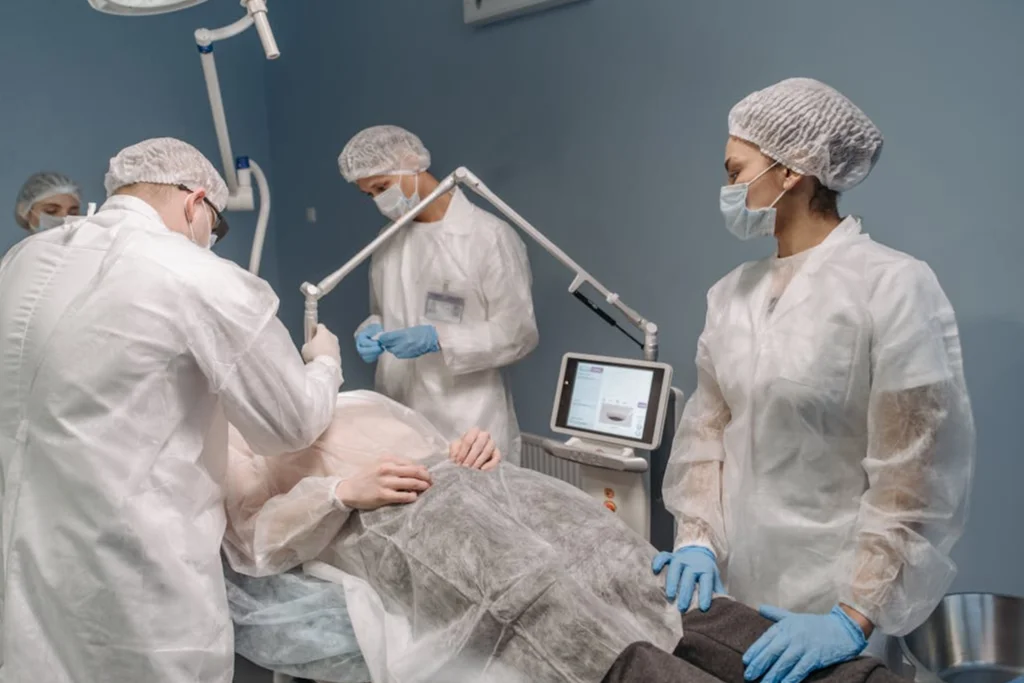

We are committed to providing world-class medical care through innovation, compassion, and unwavering dedication to our patients' wellbeing and recovery.

Every treatment plan is carefully customized to meet individual patient needs and medical history.

Surgery

Consectetur adipisci velit sed quia non numquam eius modi tempora incidunt ut labore et dolore magnam aliquam.